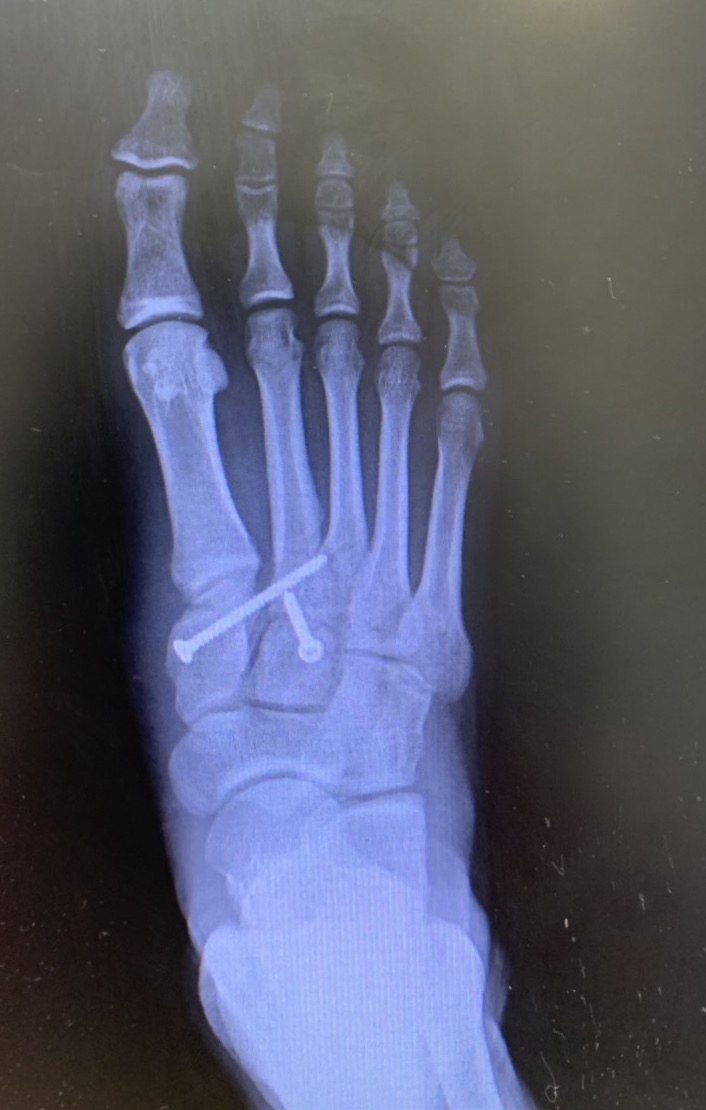

医療機関によるレントゲン、CT、MRI画像などを確認しながら医師の所見を基にリハビリ方針を決めて、各スタッフ間で情報共有して運営するよう心がけています。